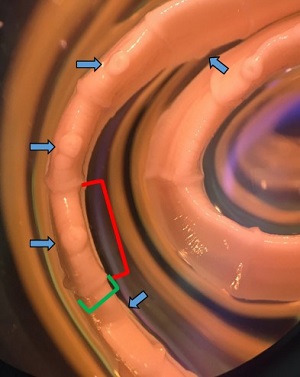

Figure C